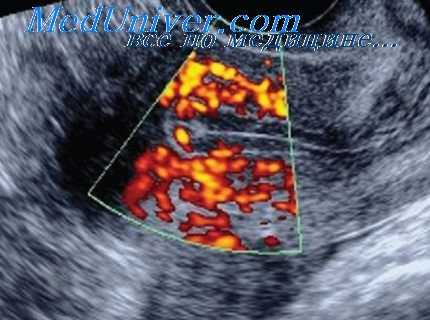

У 14 пациенток (46,6 %) в проекции придатков матки визуализировалось полостное образование с неоднородной структурой и гиперэхогенным ободком, оно встречалось у пациенток с подозрением на трубную беременность, из них у 8 (57,2 %) — с наличием умеренного количества свободной жидкости в Дугласовом пространстве (эхографический признак прерывающейся трубной беременности). При цветовом допплеровском картировании в придатковом образовании определяется зона гиперваскуляризации, которая представляет собой трофобластический кровоток.

При прерывающейся трубной беременности интенсивность цветовых сигналов значительно снижалось и определялся венозный тип кровотока у 8 пациенток (26,6 %). У 9-и пациенток (30 %) при трансвагинальном исследовании отмечалось увеличение размеров матки, утолщение срединного М-эха, из них «ложное» плодное яйцо в полости матки визуализировалось только у 2-х пациенток (22,2 %). При повторном трансвагинальном обследовании через 5 дней после первого осмотра у 6-и пациенток (20 %) визуализировалось плодное яйцо в полости матки, что подтвердило маточную беременность раннего срока. У остальных 3-х пациенток (10 %) внематочная беременность подтвердилась на операции.